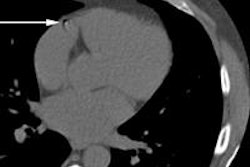

The duo's latest campaign is to question the use of electronic arrows on CT scans. Their well-written and concise editorial makes compelling reading and may well have a big impact on clinical practice. Go to our CT Community, or click here.

In cardiac imaging, a Dutch group has built an algorithm that identifies and quantifies coronary artery calcium from CT scans, paving the way for faster deployment of a test that is increasingly important in measuring the likelihood of heart disease. Get the full details here.